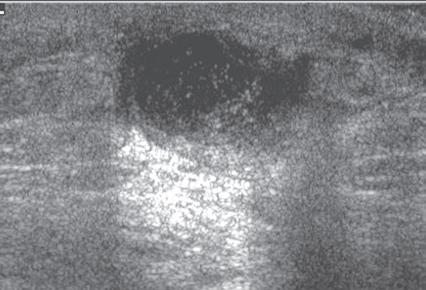

Another type of artifact is posterior acoustic enhancement or increased through-transmission. This occurs during imaging of fluid (Figs. 1.16 and 1.17) and some solid soft tissue tumors, such as peripheral nerve sheath tumors (see Fig. 2.59) and pigmented villonodular tenosynovitis (giant cell tumors of tendon sheath) (Fig. 1.18).10 In these situations, the sound beam is relatively less attenuated compared with the adjacent tissues; therefore, the deeper soft tissues will appear relatively hyperechoic compared with the adjacent soft tissues.7

FIGURE 1.18 Increased Through-Transmission. Ultrasound image of a pigmented villonodular tenosynovitis (giant cell tumor of the tendon sheath) (between × and + cursors) shows increased through-transmission (open arrows).